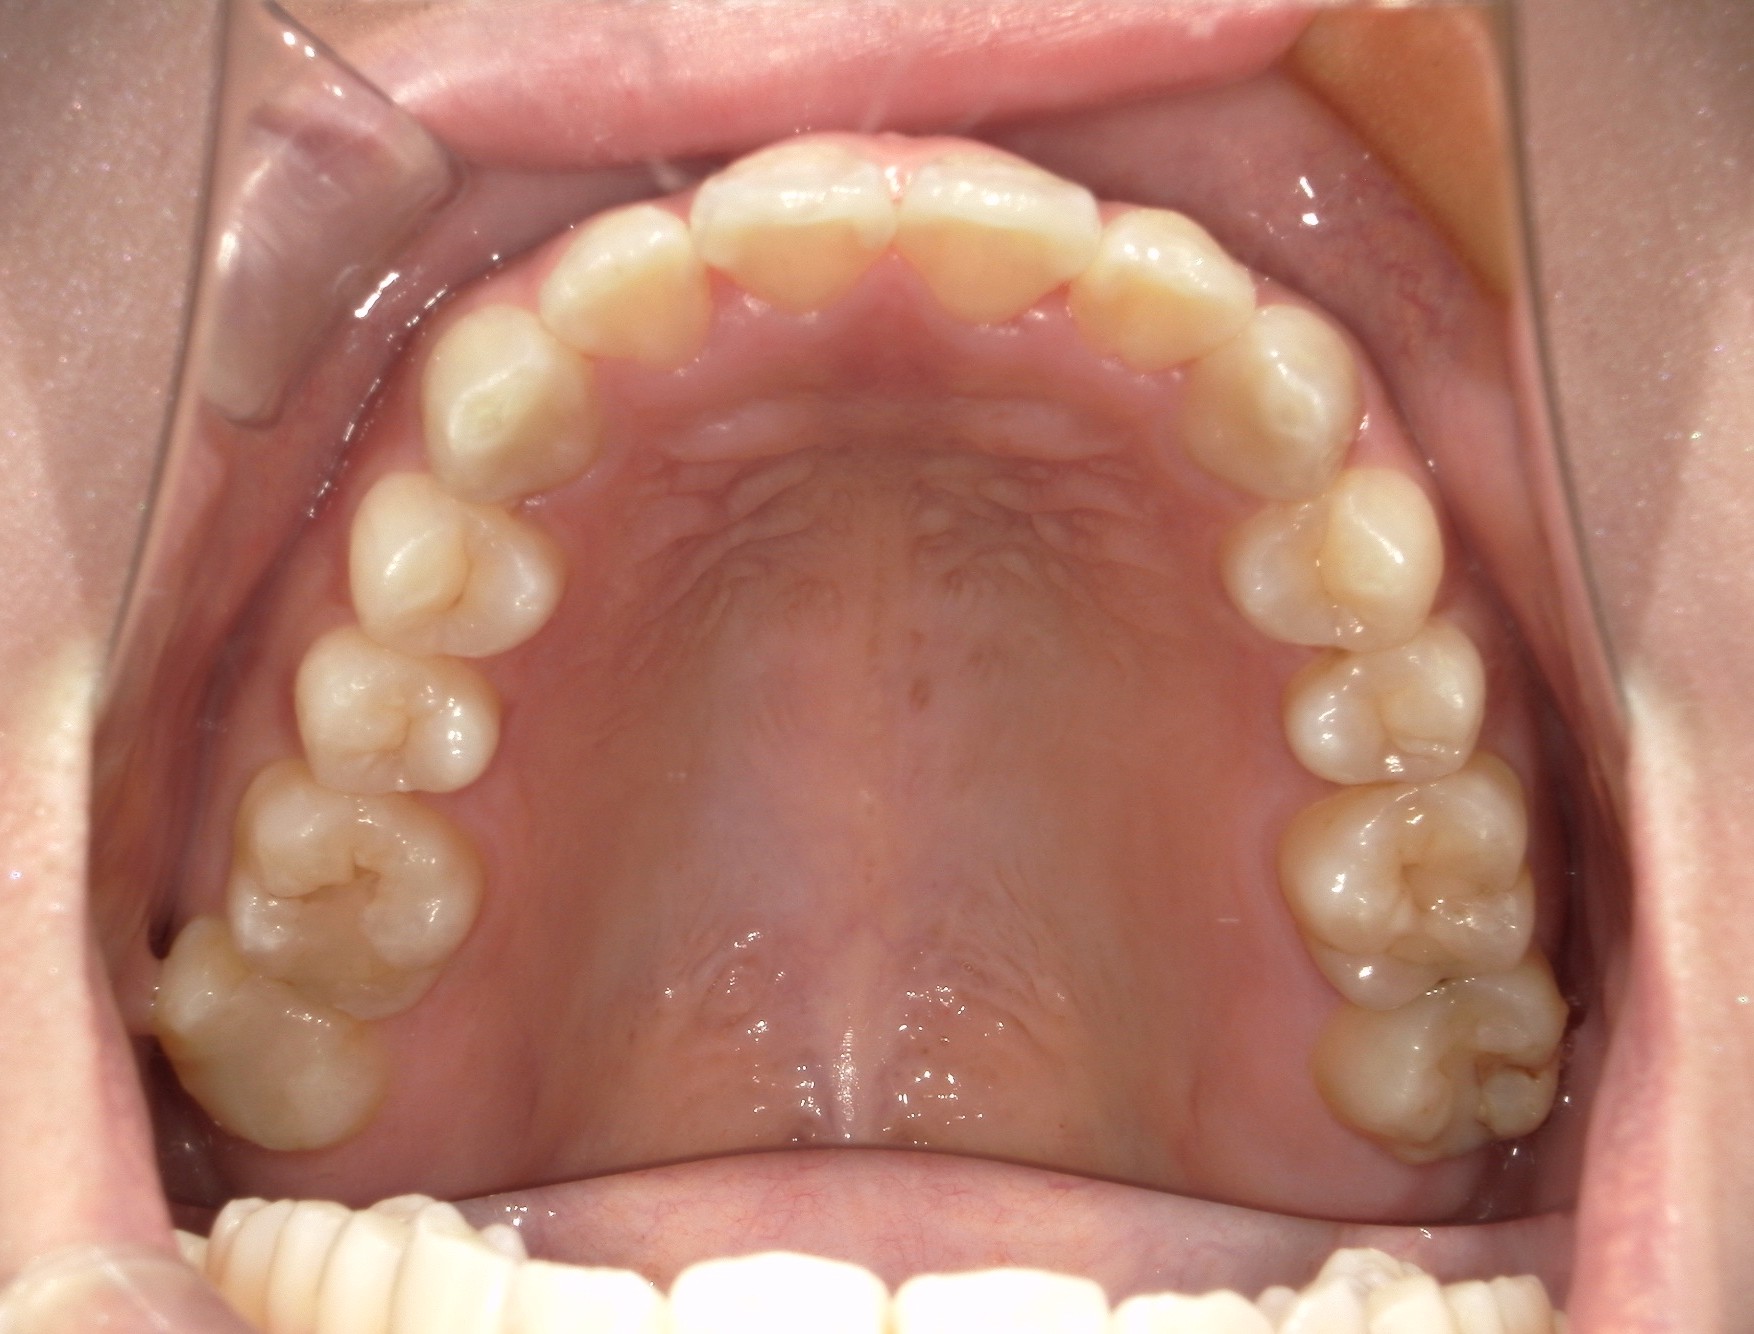

口内上

治療前

治療後